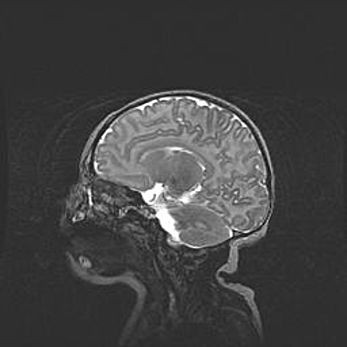

Мальформация Денди-Уокера. Киста задней черепной ямки.

Агенезия мозолистого тела.

Возраст: 2,5 месяца

Вес: 2420 г

Пол: женский

Окружность головы: 37 см

Срок гестации: 32 недели

Мальформация Денди—Уокера — редкий вид патологии ЦНС, представляющий собой врожденный порок развития каудального отдела ствола и червя мозжечка, ведущий к неполному раскрытию срединной (Мажанди) и латеральных (Лушка) апертур IV желудочка мозга. Для этогно синдрома характерна триада симптомов: гипотрофия червя мозжечка и/или полушарий мозжечка, кисты задней черепной ямки, гидроцефалия различной степени. В 70% случаев порок сочетается и с другими аномалиями головного мозга, в частности с агенезией мозолистого тела.